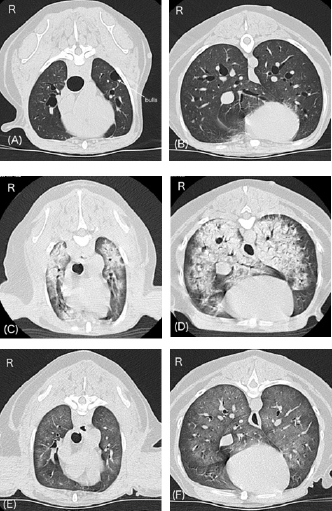

Approximately 15 minutes after being moved to the ward, the dog exhibited dyspnea and nose bleeding. The oral mucous membrane was pale, systolic blood pressure was >200 mmHg, and SpO2 ranged from 70% to 80%. The pulse rate was not recorded. A catecholamine crisis was suspected, and IV acepromazine (PromAce injectable; Boehringer Ingelheim Animal Health, Ridgefield, CT) at 0.01 mg/kg was administered for vasodilation and sedation. In addition, oxygen supply via a mask or flow-by was initiated after upper airway suctioning of blood and secretions. Following these treatments, the patient’s blood pressure decreased. Systolic and mean blood pressures were 140 and 100 mmHg, respectively. However, SpO2 remained at approximately 90% despite oxygen therapy, and respiratory distress was evident. Lung ultrasonography (LOGIQ e Premium; GE HealthCare, Tokyo, Japan) revealed a shred sign suggestive of lung consolidation with aeration in the left caudodorsal and perihilar lung regions. Multiple B lines suggestive of a wet lung were also observed in the left lung. The awake CT images taken 90 minutes after anesthetic recovery showed severe pulmonary consolidation with air bronchograms throughout all lung fields (Fig. 2C and D), and a decision was made to initiate ventilatory support under stable hemodynamics. Blood sampling for measurement of plasma catecholamine levels could not be performed given that our top priority was to stabilize a critical hypoxemia following the hypertensive crisis.

Fig. 2. Changes in lung CT images over time. A and B, images with breath hold at 10 cm H2O under general anesthesia before a hypertensive crisis. C and D, awake images 75 minutes after the onset of respiratory failure following a hypertensive crisis. E and F, images under spontaneous breathing 24 hours after onset of respiratory failure. Panels A, C, and E, cranial level; panels B, D, and F, caudal level. A and B show normal canine lungs except for the presence of bulla. C and D reveal acute onset of severe pulmonary consolidation with air bronchograms throughout all lung fields compared with A and B. E and F reveal dramatic improvement of pulmonary consolidation compared with C and D.

On the morning after 14 hours of ICU ventilation, PaO2 and PaCO2 were 93 and 33 mmHg, respectively. The P/F ratio was calculated to be 310. The ventilatory settings were: ΔPsupport, 7 cm H2O; CPAP, 5 cm H2O; and FiO2, 0.3. No cardiorespiratory instability was observed. In addition, only a few B lines were observed on lung ultrasonography. Improvement in the pulmonary CT images was also noted (Fig. 2E and F). Therefore, an attempt to wean the patient from the ventilator was initiated 15 hours after starting ICU ventilation (24 hours after the onset of respiratory failure). To allow weaning from the ventilator, constant-rate infusions were discontinued. Ten minutes later, the patient was no longer accepting the endotracheal tube, at which time the patient was extubated. Blood sputum adhesion was observed at the tip of the extubated tube. The patient was able to breathe effectively with some respiratory effort, and SpO2 was 96% under nasal oxygen supply at 0.5 l/minute. PaO2 and PaCO2 were 77 and 27 mmHg, respectively. The body weight after weaning was 170 g less than that before the onset of respiratory failure. Cefazoline and enrofloxacin (Baytril 2.5% injection for dogs and cats; Elanco Japan, Tokyo, Japan) were administered as prophylactic antibiotics during hospitalization. In addition, oral treatment with pimobendane (VETMEDIN chewable tablet; Boehringer Ingelheim Animal Health, Tokyo, Japan) was resumed. Oxygen therapy was continued for 24 hours after extubation. Finally, the dog was discharged 3 days after weaning from ventilation. The owner refused additional treatment for the intra-abdominal lesions. The dog survived without any respiratory or neurological complications for 14 months after weaning from mechanical ventilation.